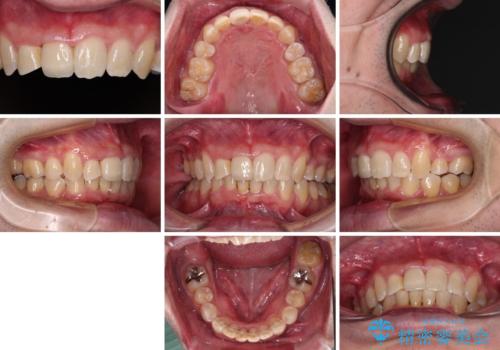

矯正治療後にはオーダーメイドタイプのオールセラミッククラウンを装着し、自然な口元に仕上がりました。